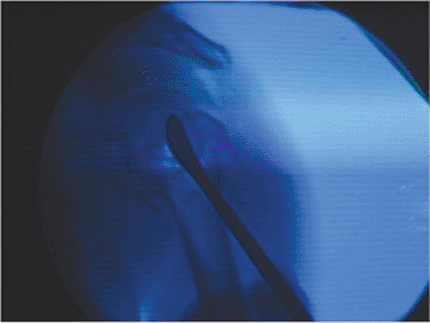

glenoid must be possible with an image intensifier. The image

intensifier is placed parallel to the table at the patient’s head on

the injured side (Fig. 3.6). With this

arrangement, imaging in the AP and axillary planes is possible. Some

surgeons prefer to bring the c-arm from the opposite side and obtain

images in the AP and transscapular lateral planes, but this approach

does not image the humeral head quite, as well as the axillary lateral

view. In either position, trial images should be obtained prior to

prepping.